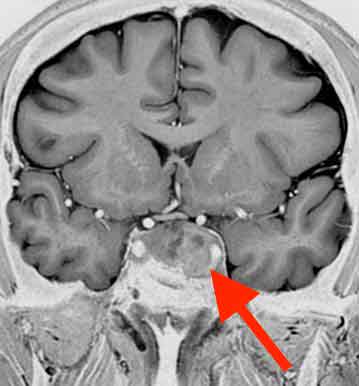

50代の男性で、20代の頃から片頭痛と診断されていた方です。

何となく左側の視野が見えにくいと感じる事が多く、片頭痛で通院している当院へ相談されました。

頭部MRI検査を行ったところ、

下垂体腺腫という腫瘍がありました。

本来良性の腫瘍で、急速に悪化する事はありません。しかし、左側の視野が欠ける症状があったため、手術のできる病院へ紹介させていただきました。